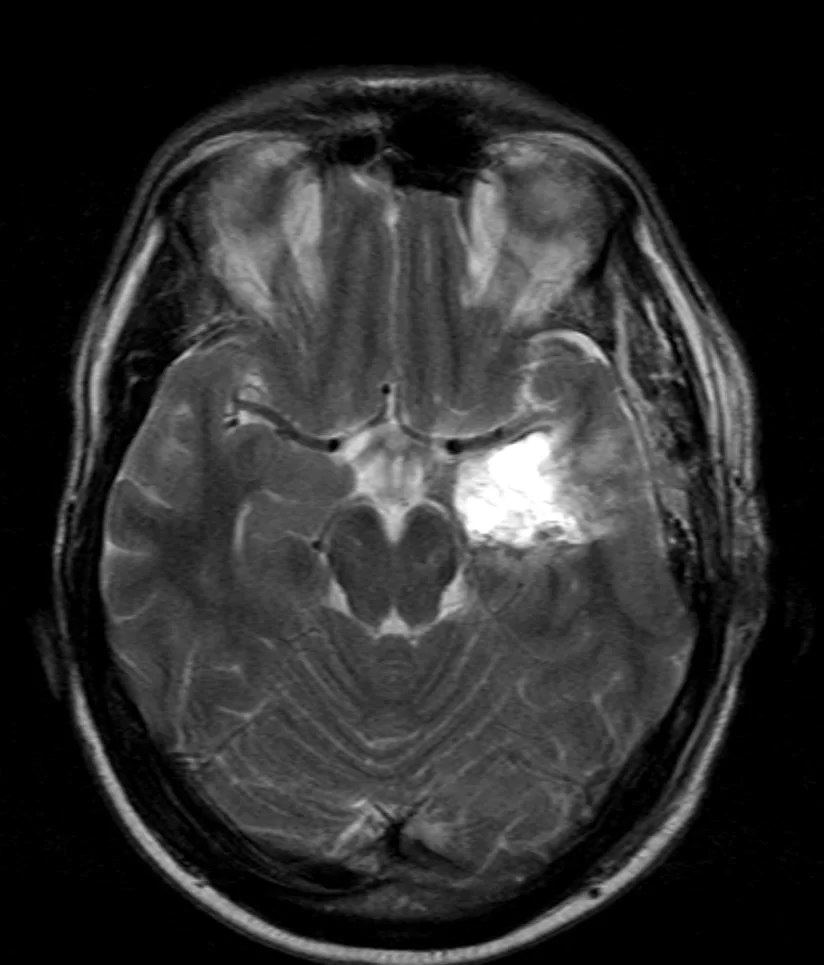

Η μετεγχειρητική μαγνητική τομογραφία εγκεφάλου δείχνει την πλήρη εξαίρεση της βλάβης με διατήρηση του νεοφλοιού. Η ιστολογική εξέταση ανέδειξε γαγγλιογλοίωμα WHO I καθώς επίσης και στοιχεία σκλήρυνσης του ιπποκάμπου.

Στην περίπτωση αυτή η βλάβη είναι εν τω βάθει, δηλαδή αρκετά βαθιά στον εγκέφαλο, σε μια περιοχή του κροταφικού λοβού που ονομάζεται «ιππόκαμπος». Αποφασίσαμε να εφαρμόσουμε μια χειρουργική τεχνική η οποία θα μας επέτρεπε να προσπελάσουμε και να αφαιρέσουμε τη βλάβη, χωρίς να προκαλέσουμε ζημιά στον υπερκείμενο εγκεφαλικό φλοιό ο οποίος ήταν υγιής. Η εναλλακτική θα ήταν η λεγόμενη φλοιο-αμυγδαλοιπποκαμπεκτομή, όπου ο νεοφλοιός του κροταφικού πόλου αφαιρείται.